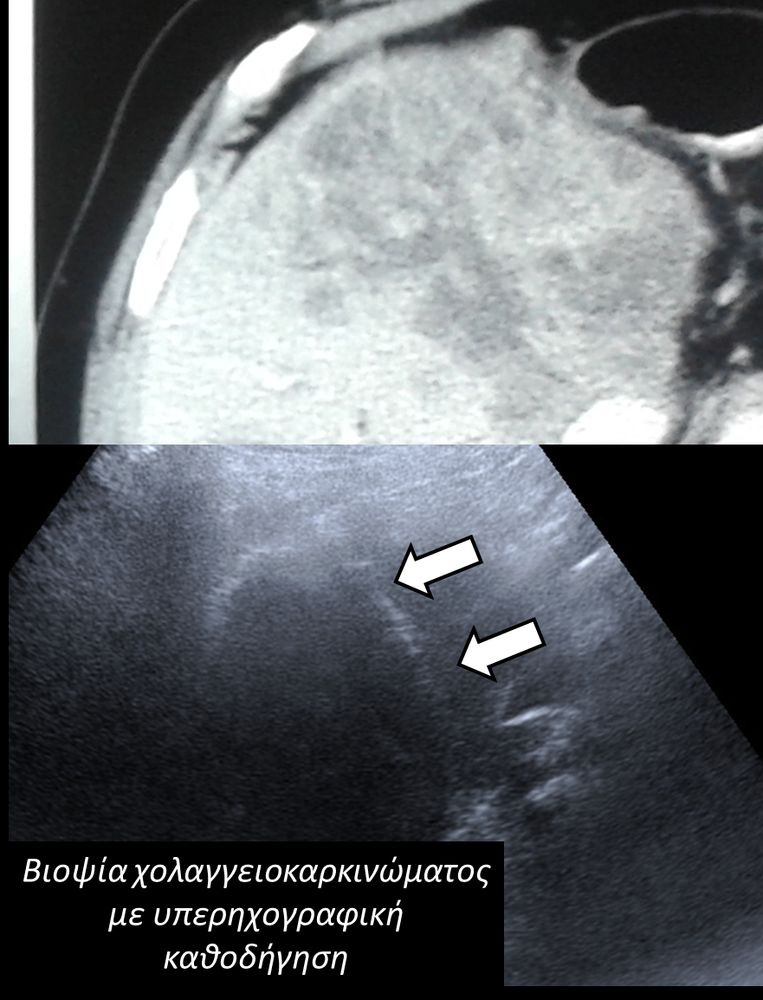

Η διαδερμική βιοψία είναι μία ελάχιστα επεμβατική μέθοδος λήψης υλικού από τον όγκο για κυτταρολογική και ιστολογική εξέταση, από εστιακές αλλοιώσεις του ήπατος, πνεύμονα, νεφρού κλπ. Συστήνεται από τον κλινικό ιατρό ανάλογα με το είδος και το μέγεθος της βλάβης και πραγματοποιείται με ασφάλεια από επεμβατικό ακτινολόγο με την καθοδήγηση αξονικού τομογράφου ή υπερήχων. Στη σύγχρονη ογκολογική θεραπεία όπου γίνεται προσπάθεια καταπολέμησης του καρκίνου σε μοριακό επίπεδο κρίνεται αναγκαία η ακριβής ιστολογική ταυτοποίηση του όγκου ώστε να εφαρμοσθεί εξατομικευμένη θεραπεία για το βέλτιστο αποτέλεσμα. Οι κατευθυνόμενες βιοψίες στοχευουν στο να παρέχουν στον κλινικό ογκολόγο το απαραίτο ιστοπαθολογικό υλικό που θα του επιτρέψει να εφαρμόσει την κατάλληλη θεραπεία για τον ογκολογικό ασθενή.